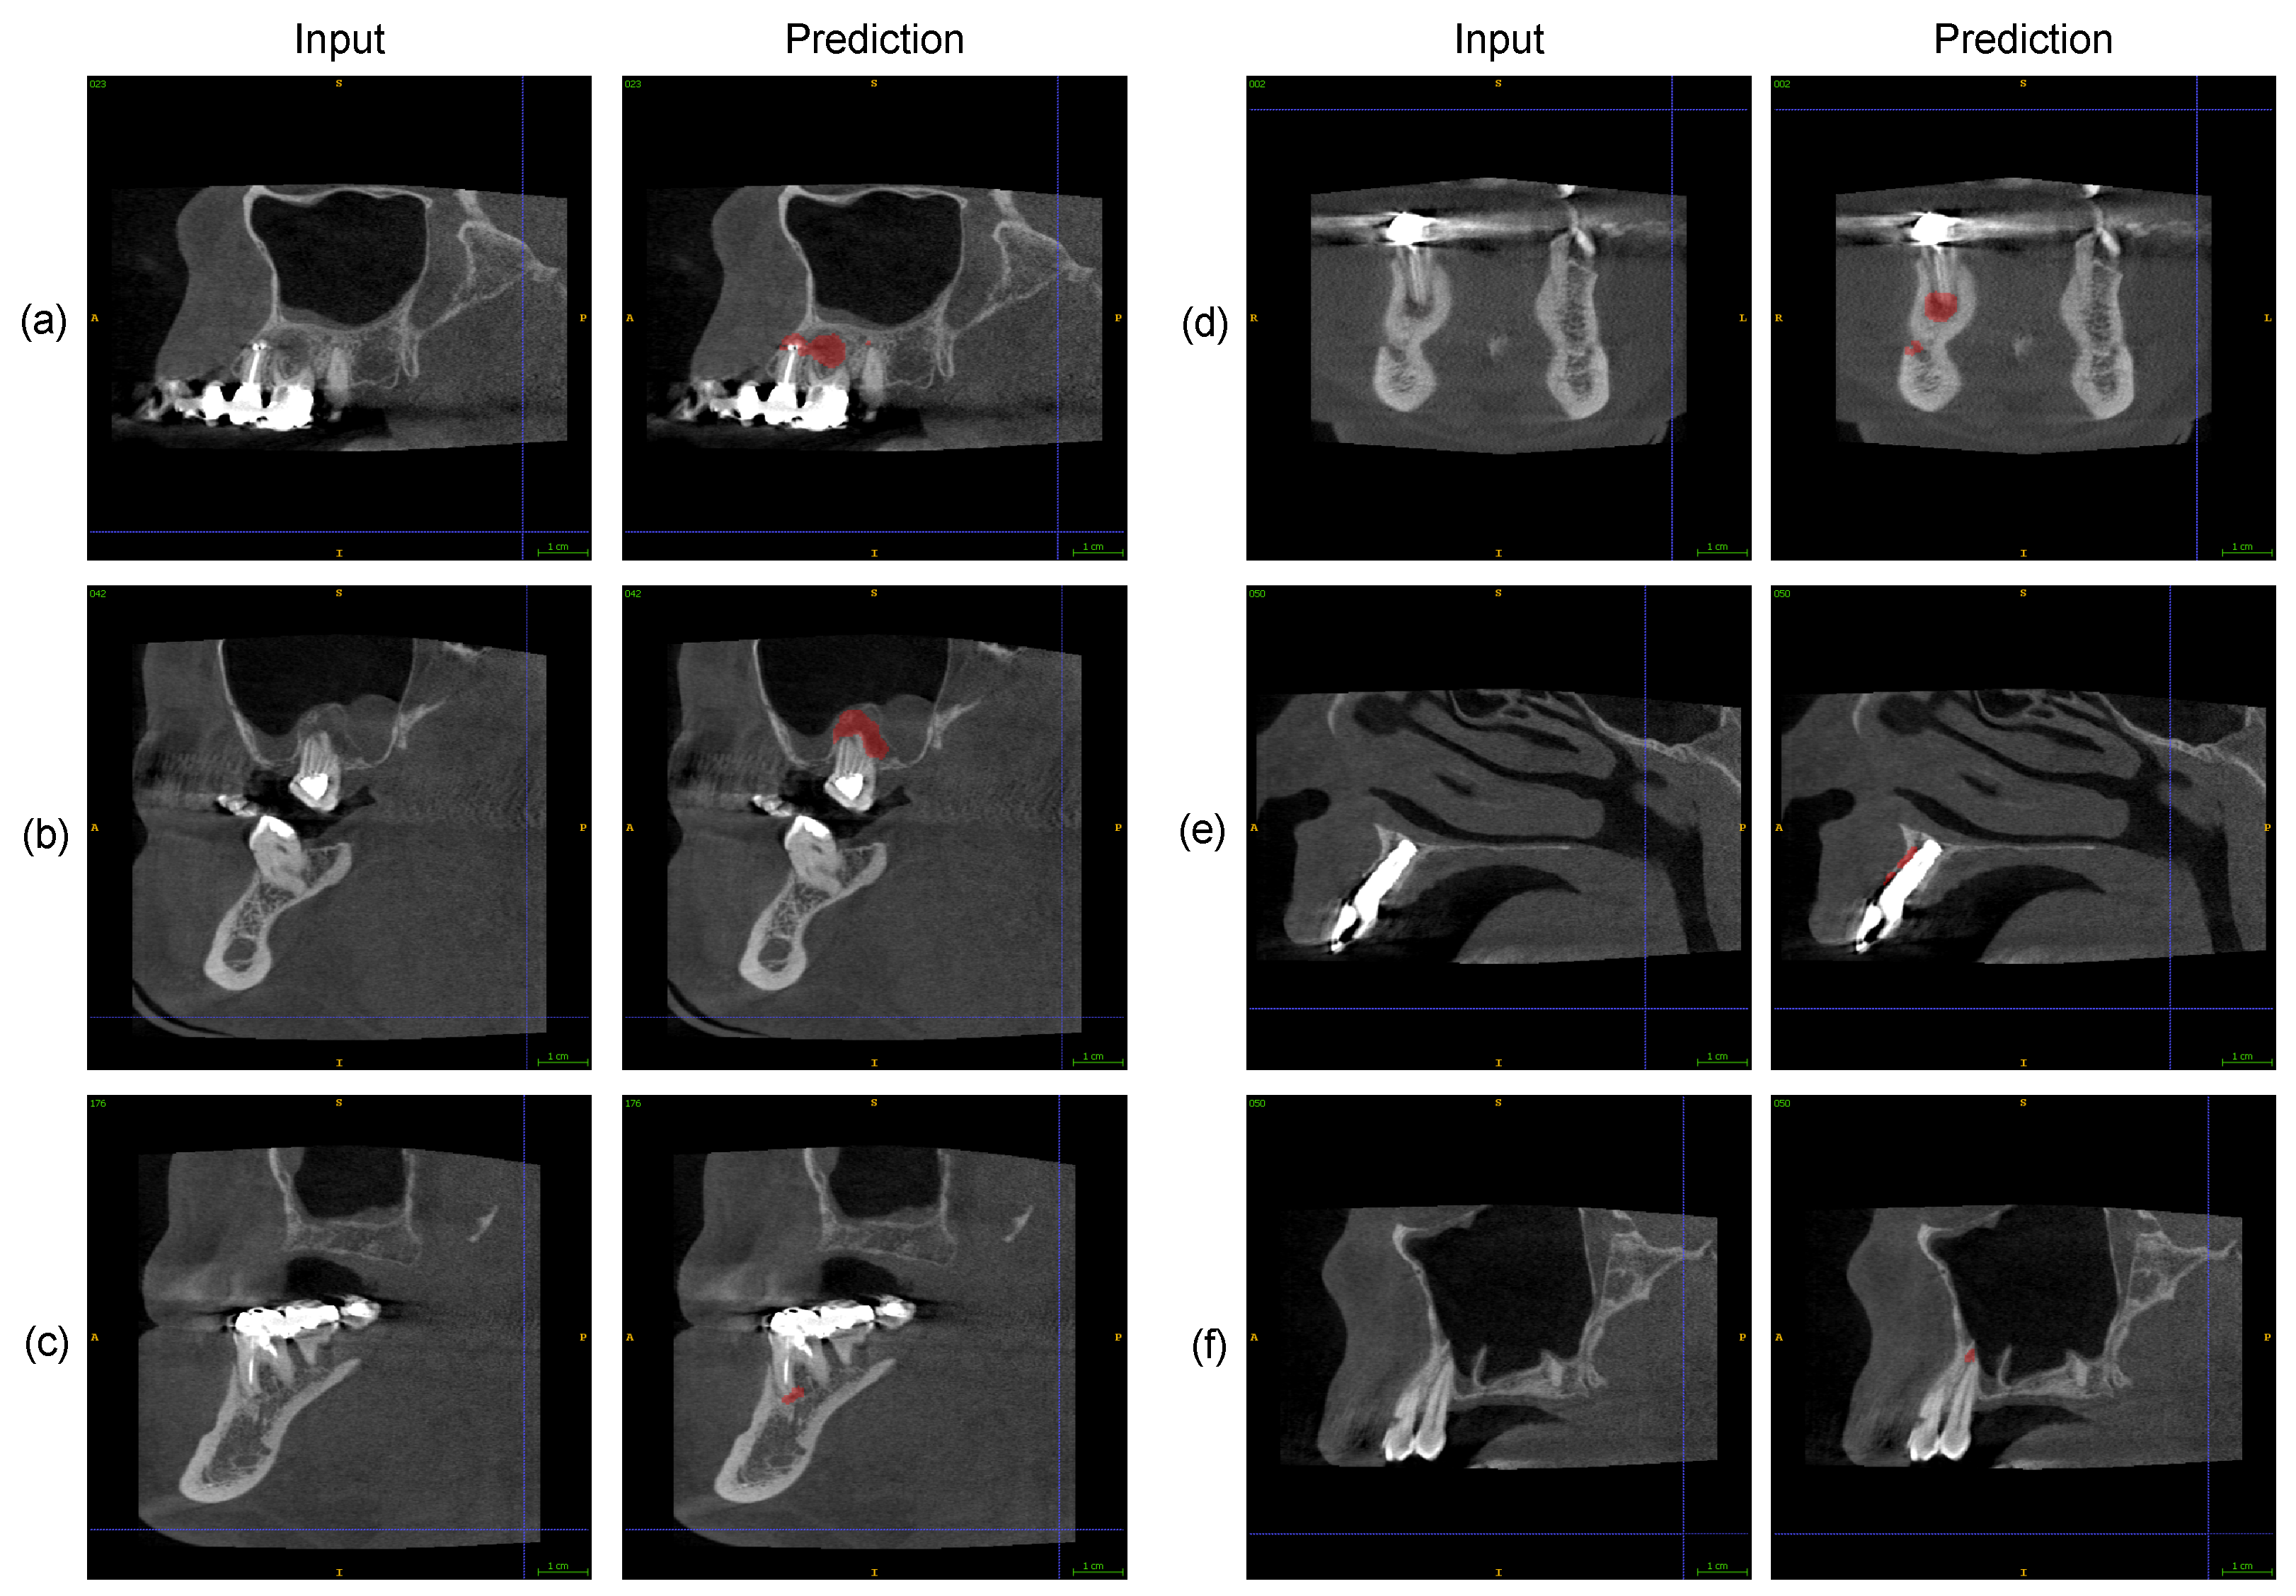

2.4. Automatic PAL Detection

2.5. Expert Assessment of Software PAL Detections

3. Results